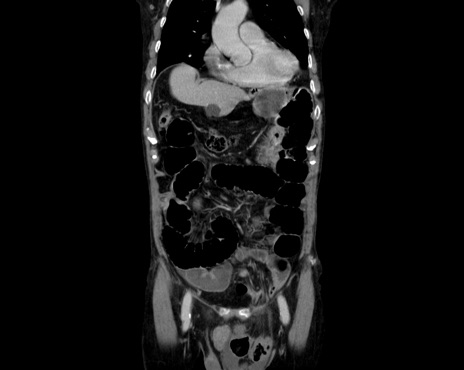

症例26(冠状断像)

【症例】80歳代男性

【主訴】嘔吐

【現病歴】昨晩2回嘔吐あり、今朝になっても嘔吐あり。来院。

【既往歴】胃潰瘍

【身体所見】意識清明、BT 37.6℃、BP 166/95mmHg、HR 100bpm、SpO2 97%、腹部:平坦・軟、腸蠕動音聴取良好、圧痛なし。

【データ】WBC 21900、CRP 1.4